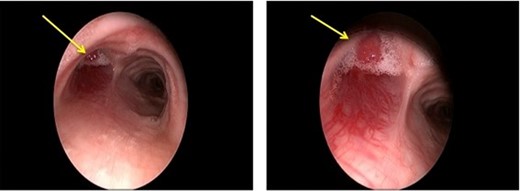

Rigid bronchoscopy was performed, confirming an intraluminal hypervascular mass occluding the entire left main-stem bronchus with visible vasculature extending into the posterior tracheal wall. The mass had a smooth appearance with telangiectasias and extensive friability (Fig. 2). A biopsy of the mass suggested an atypical neuro-endocrine tumor.